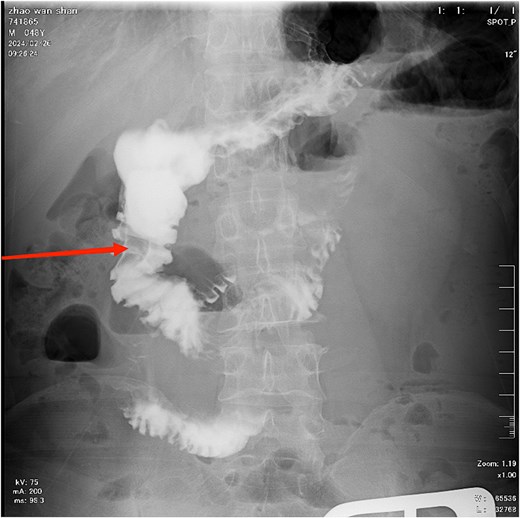

The patient, male, 48 years old, rural household registration. The patient was admitted with persistent epigastric pain and discomfort lasting over 5 days. He had a 3-year history of diabetes mellitus, regularly managed with oral metformin, and maintained good glycemic control. He had a history of diabetes for 3 years, regularly took metformin orally, and his blood glucose was well controlled. The patient complained of persistent abdominal pain and discomfort after eating 5 days ago, with abdominal distension and occasional nausea, no vomiting, diarrhea, hematochezia, acid regurgitation, hiccups, belching, chills, and fever. Since the onset of the disease, the patient's spirit, appetite, and sleep were poor, no stool, and normal urination. The weight did not drop. The physical examination showed normal temperature, slightly raised upper abdomen, visible intestinal type, no peristalsis wave, total abdominal tenderness (+), mainly in the upper abdomen, no muscle tension and rebound pain, mobile murmur (−), bowel sound hyperactivity, and the sound of air over water could be heard. Auxiliary examination: abdominal computed tomography (CT) suggested: gallbladder stones, intestinal obstruction, and uneven thickening of intestinal wall (Fig. 1).

CT demonstrates features of intestinal obstruction as marked by the white arrow.